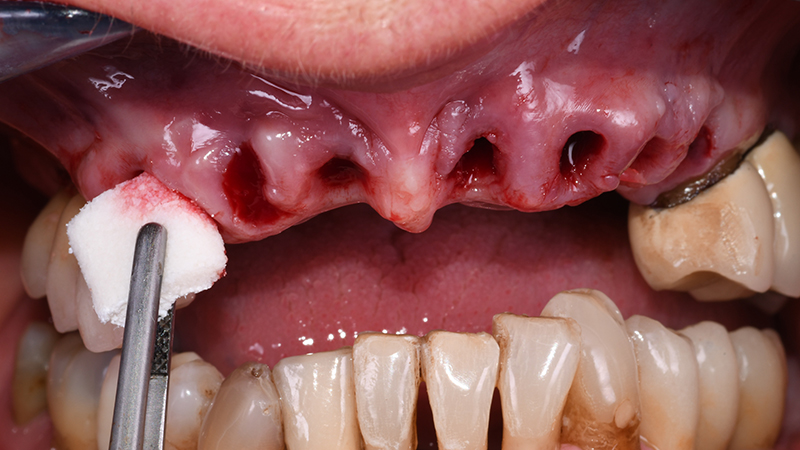

In seguito ad anestesia per infiltrazione mediante articaina cloridrato + vasocostrittore (adrenalina 1:100.000), sono state eseguite le estrazioni degli elementi interessati (Fig. 6).

Fig. 6 - Alveoli post-estrattivi prima di applicare R2Guide®

Le fixtures implantari sono state inserite seguendo il planning pre-chirurgico (Figs. 10, 11) in posizione 13-21-23-24. Lo spazio presente tra la componente vestibolare di ciascun impianto e l’osso vestibolare (jumping distance) e gli alveoli post-estrattivi non riceventi impianti, hanno ricevuto l’innesto di sostituto osseo xenogenico collagenato di origine suina (The Graft, Purgo, Challans, Francia) (Figs. 12, 13, 14) dopo aver posizionato i Multi-Unit abutment (MUA). La protesi provvisoria è stata avviata entro 24 ore dal termine della chirurgia (Figs. 15, 16).

Fig. 12 - Sostituto osseo collagenato in blocco The Graft Purgo Biologics

Fig. 13 - Applicazione di sostituto osseo collagenato